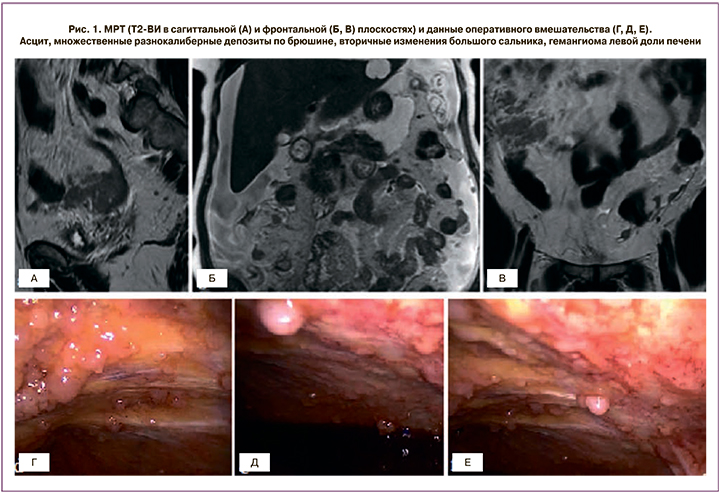

Утолщение брюшины, наличие узлов в ее структуре, мягкотканные включения на уровне большого сальника, асцит – основные признаки вторичного поражения брюшины (рис. 1). Существует три типа имплантов: солидные, кистовидные и смешанные, а также различные паттерны метастазирования: нодулярный тип при наличии узловых мягкотканных включений по ходу брюшины округлой или овальной формы со спикулообразными краями или сливное поражение с диффузным неравномерным утолщением листков. Изменение толщины перитонеальных листков может наблюдаться после хирургических вмешательств или внутрибрюшной химиотерапии. Как правило, фокусы перитонеального канцероматоза более доступны оценке в перпендикулярных к изучаемому участку срезах.

Признаки поражения большого сальника варьируют от тяжистой исчерченности жировой клетчатки до многоузловых или сливных депозитов с формированием «сальникового пирога» (рис. 3).